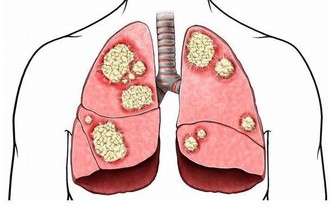

放射科醫師沒有發現任何異常,但醫生擔心她可能患有腦脊液滲漏,並將她介紹給一位腦科醫生,後者證實了這些懷疑。CT實際上顯示她頭骨中有一個小骨縫隙,腦液從她的鼻子裡流出來。

由於她的腦液是自發性洩漏,意味著她沒有造成先前創傷。這種情況很罕見,儘管它往往發生在肥胖或超重的中年女性身上(腹部的重量對靜脈有壓力,並且壓力傳遞到大腦中),但這位女性並不符合這一概況。然而,CT掃描表明,她的大腦內層突出進入了她的竇腔,內膜上出現了微小的撕裂,讓液體從她的大腦流入鼻子。

液體樣品證實了β-2轉鐵蛋白的存在,該蛋白僅在眼睛、肝臟和腦液中可以發現。如果你遇到它從鼻子裡冒出來,要知道它來自大腦。

如果不做手術來修復這個撕裂,這位病人就有腦膜炎的風險,或者腦部膿腫——感染可能很容易從她的鼻子傳播到插入她鼻竇區域的脆弱組織。於是,醫生迅速為她進行了手術,並且成功制止了這種不同尋常的液體再從鼻孔流出來。

然而,醫生仍然不知道為什麼她出現了異常高的腦液壓,可能是她的頭骨上日積月累的壓力所導致。